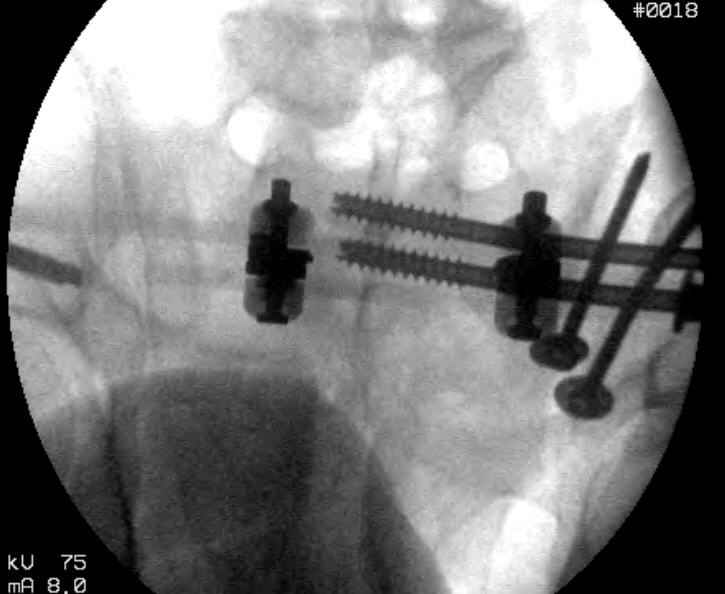

Hello gentlemen- Case is 52 YO male, fell out of treestand while deerhunting. He is 6 ft, approx. 260-275 lbs. Was hemodynamic unstable at local ER, sent to our Trauma center where circumferential pelvic binder placed and pt. stabilized with fluid, blood, and rewarming. Angiography not performed. An extraperitoneal bladder disruption was found, uro elected to treat non-operatively. Initial xray (not shown) demonstrated 5-7 cm wide at symphysis and SI joint. The first image attached is of CT once binder is in place. On post trauma day 5 the pt was taken to OR for ORIF of his iliac wing fracture and SI dislocation. The swelling/3rd spacing of fluid in the area of symphysis was profound, but quite acceptable posteriorly. Patient was prone for procedure, as I thought too difficult to fix the wing in lateral position. Of course the repair of wing was easy, but reduction of SI very demanding. The Floro images document the residual lack of reduction. That was the closest I could get it using 6mm joystick in wing, and clamp on sacrum and clamp through notch. The fixation was (initially) rigid. Anterior ex fix with supra-acetabular pins was placed due to condition of soft tissues, massive "beer-belly" overhanging the crest. Post trauma day ten patient's xray shows failure of posterior construct. Plan was to perform revision orif once soft tissues resolve considerably for full anrterior fixation and posterior fixation. However, while Im away for holiday (on Post trauma day 15), pt is developing septic clinical appearance, and trauma suspects pelvic abcess near symphysis and performs I and D - finds nothing but no primary closure performed. Posterior tissues/incision continue to look healthy. Now is post trauma day 17, pt is still tubed/on dopamine/and wbc still elevated, anterior incision still packed open. Clearly must get to bottom of possible sepsis, but then what? Thanks for you time - sorry for such lengthy clinical description. Thomas Schaller Kalamazoo, Michigan

5. Your caudal iliosacral screw is/was in his spinal canal... it's low and posterior and the lateral fluoro image confirms this... a postop CT will show it (or it's trail at this point)... canal screws do not hold.

6. Frames (even fancy new-style low ones) have poor mechanical stability when compared to symphyseal internal fixation...unstable rings in fat (and skinny) folks demand stable anterior and posterior stabilities... a frame

can't get you there... consider it a helper/support at best.